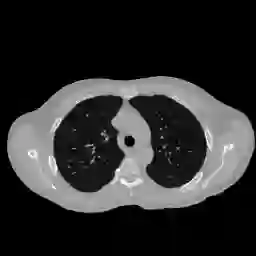

Anatomically consistent field-of-view (FOV) completion to recover truncated body sections has important applications in quantitative analyses of computed tomography (CT) with limited FOV. Existing solution based on conditional generative models relies on the fidelity of synthetic truncation patterns at training phase, which poses limitations for the generalizability of the method to potential unknown types of truncation. In this study, we evaluate a zero-shot method based on a pretrained unconditional generative diffusion prior, where truncation pattern with arbitrary forms can be specified at inference phase. In evaluation on simulated chest CT slices with synthetic FOV truncation, the method is capable of recovering anatomically consistent body sections and subcutaneous adipose tissue measurement error caused by FOV truncation. However, the correction accuracy is inferior to the conditionally trained counterpart.

翻译:按比例一致的FOV完成可以恢复被截断的身体部位,对于受限FOV的计算机断层扫描(CT)进行定量分析具有重要应用。 现有的基于条件生成模型的解决方案依赖于训练阶段合成截断模式的保真度,这为该方法的泛化能力到未知类型的截断带来了限制。 在这项研究中,我们评估了一种基于预训练的无条件生成扩散优先的零样本方法,在推理阶段可以指定任意形式的截断模式。 通过在模拟胸部CT切片上进行评估,该方法能够恢复按比例一致的身体部位和由FOV截断引起的皮下脂肪组织测量误差。 然而,纠正精度不如有条件的训练对照组。